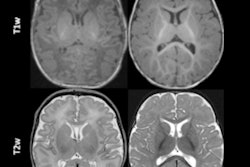

In collaboration with Philips Healthcare and Futura, the investigators developed a new MRI method that uses a special head scanner. The method places numerical values on MRI images of the brain to show how much myelin is present in a particular area compared to other areas of the image – for example, a number eight means that "the myelin content at this point is only 8% of a maximum value of 100, which indicates a significant thinning of the myelin sheaths," they wrote.